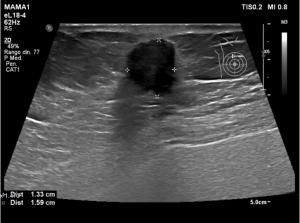

Explicación: Tras ver una lesión, se hace una ecografía para diferenciar si es un nódulo maligno o simplemente un quiste.